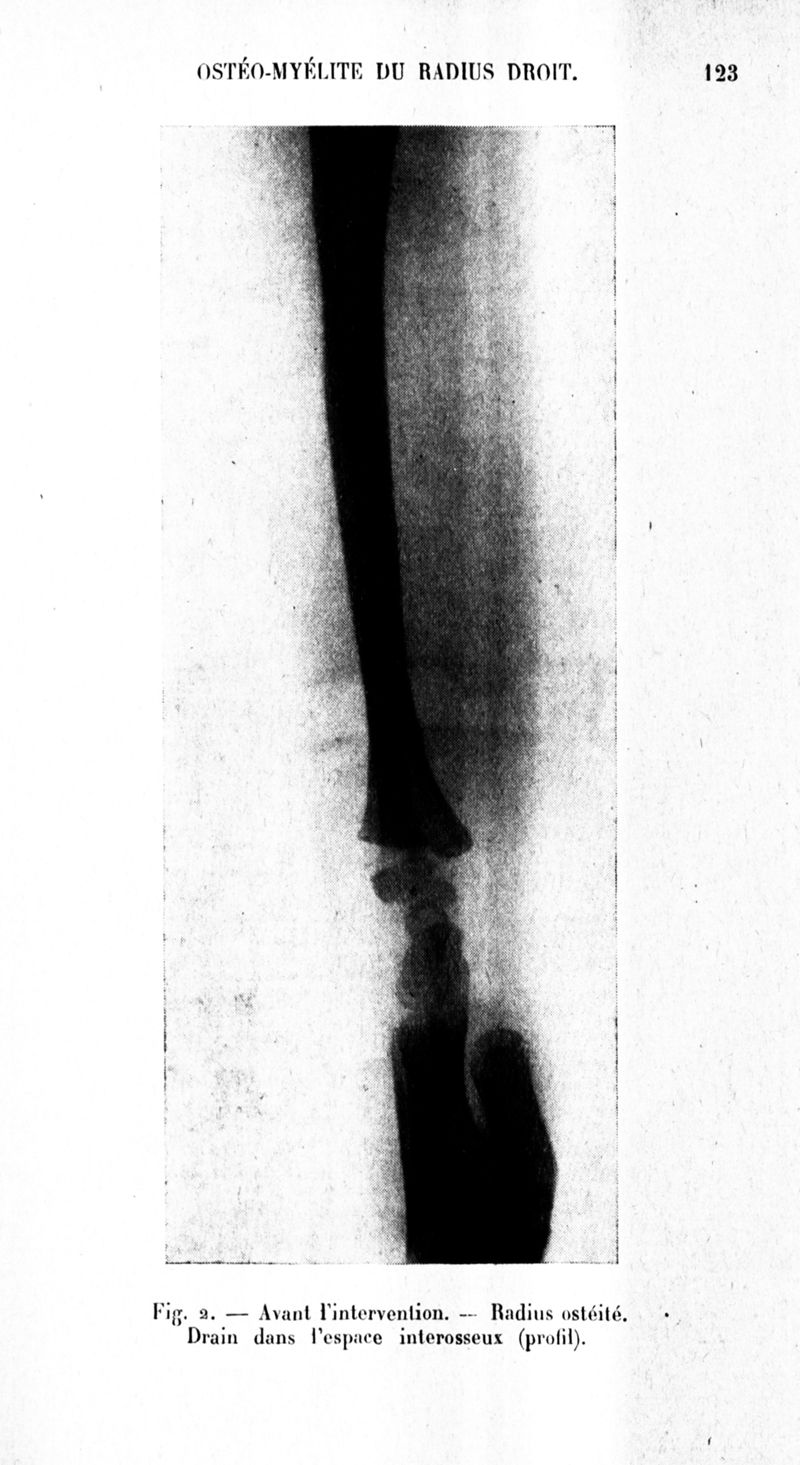

Archives de médecine et pharmacie navales

1937, n° 127. - Paris : Imprimerie nationale, 1937.